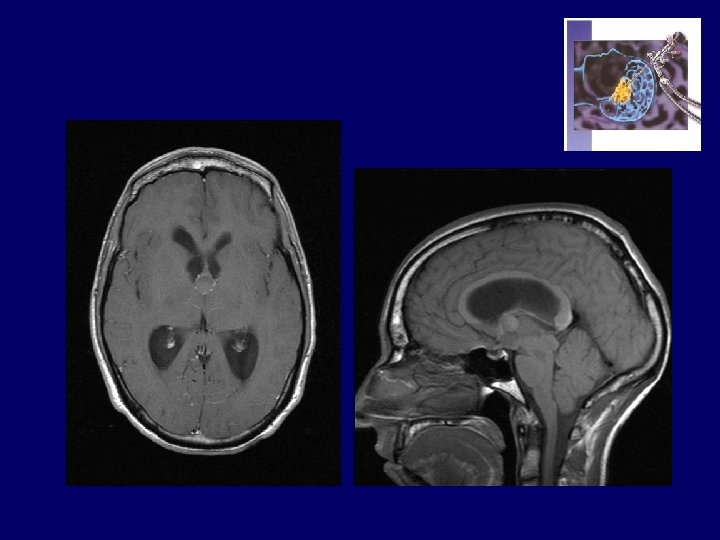

Obs. ZI…. Thomas ( 13 - 01 1992 ) • At 6 yrs : headaches, drowsiness, rapid visual deterioration • 24 -08 -1998 : OD = 4/10 OG = 2/10 • CT and MRI : Craniopharyngioma Hydrocephalus • 30 -08 -1998 : OD = 1/20 OG = 1/10 VP Shunt • 02 -09 -1998 : OD = 3/10 OG = 2/10 • 03 -09 -1998 : Total resection of C. • 18 -02 -1999 : OD = 1/30 OG = 0